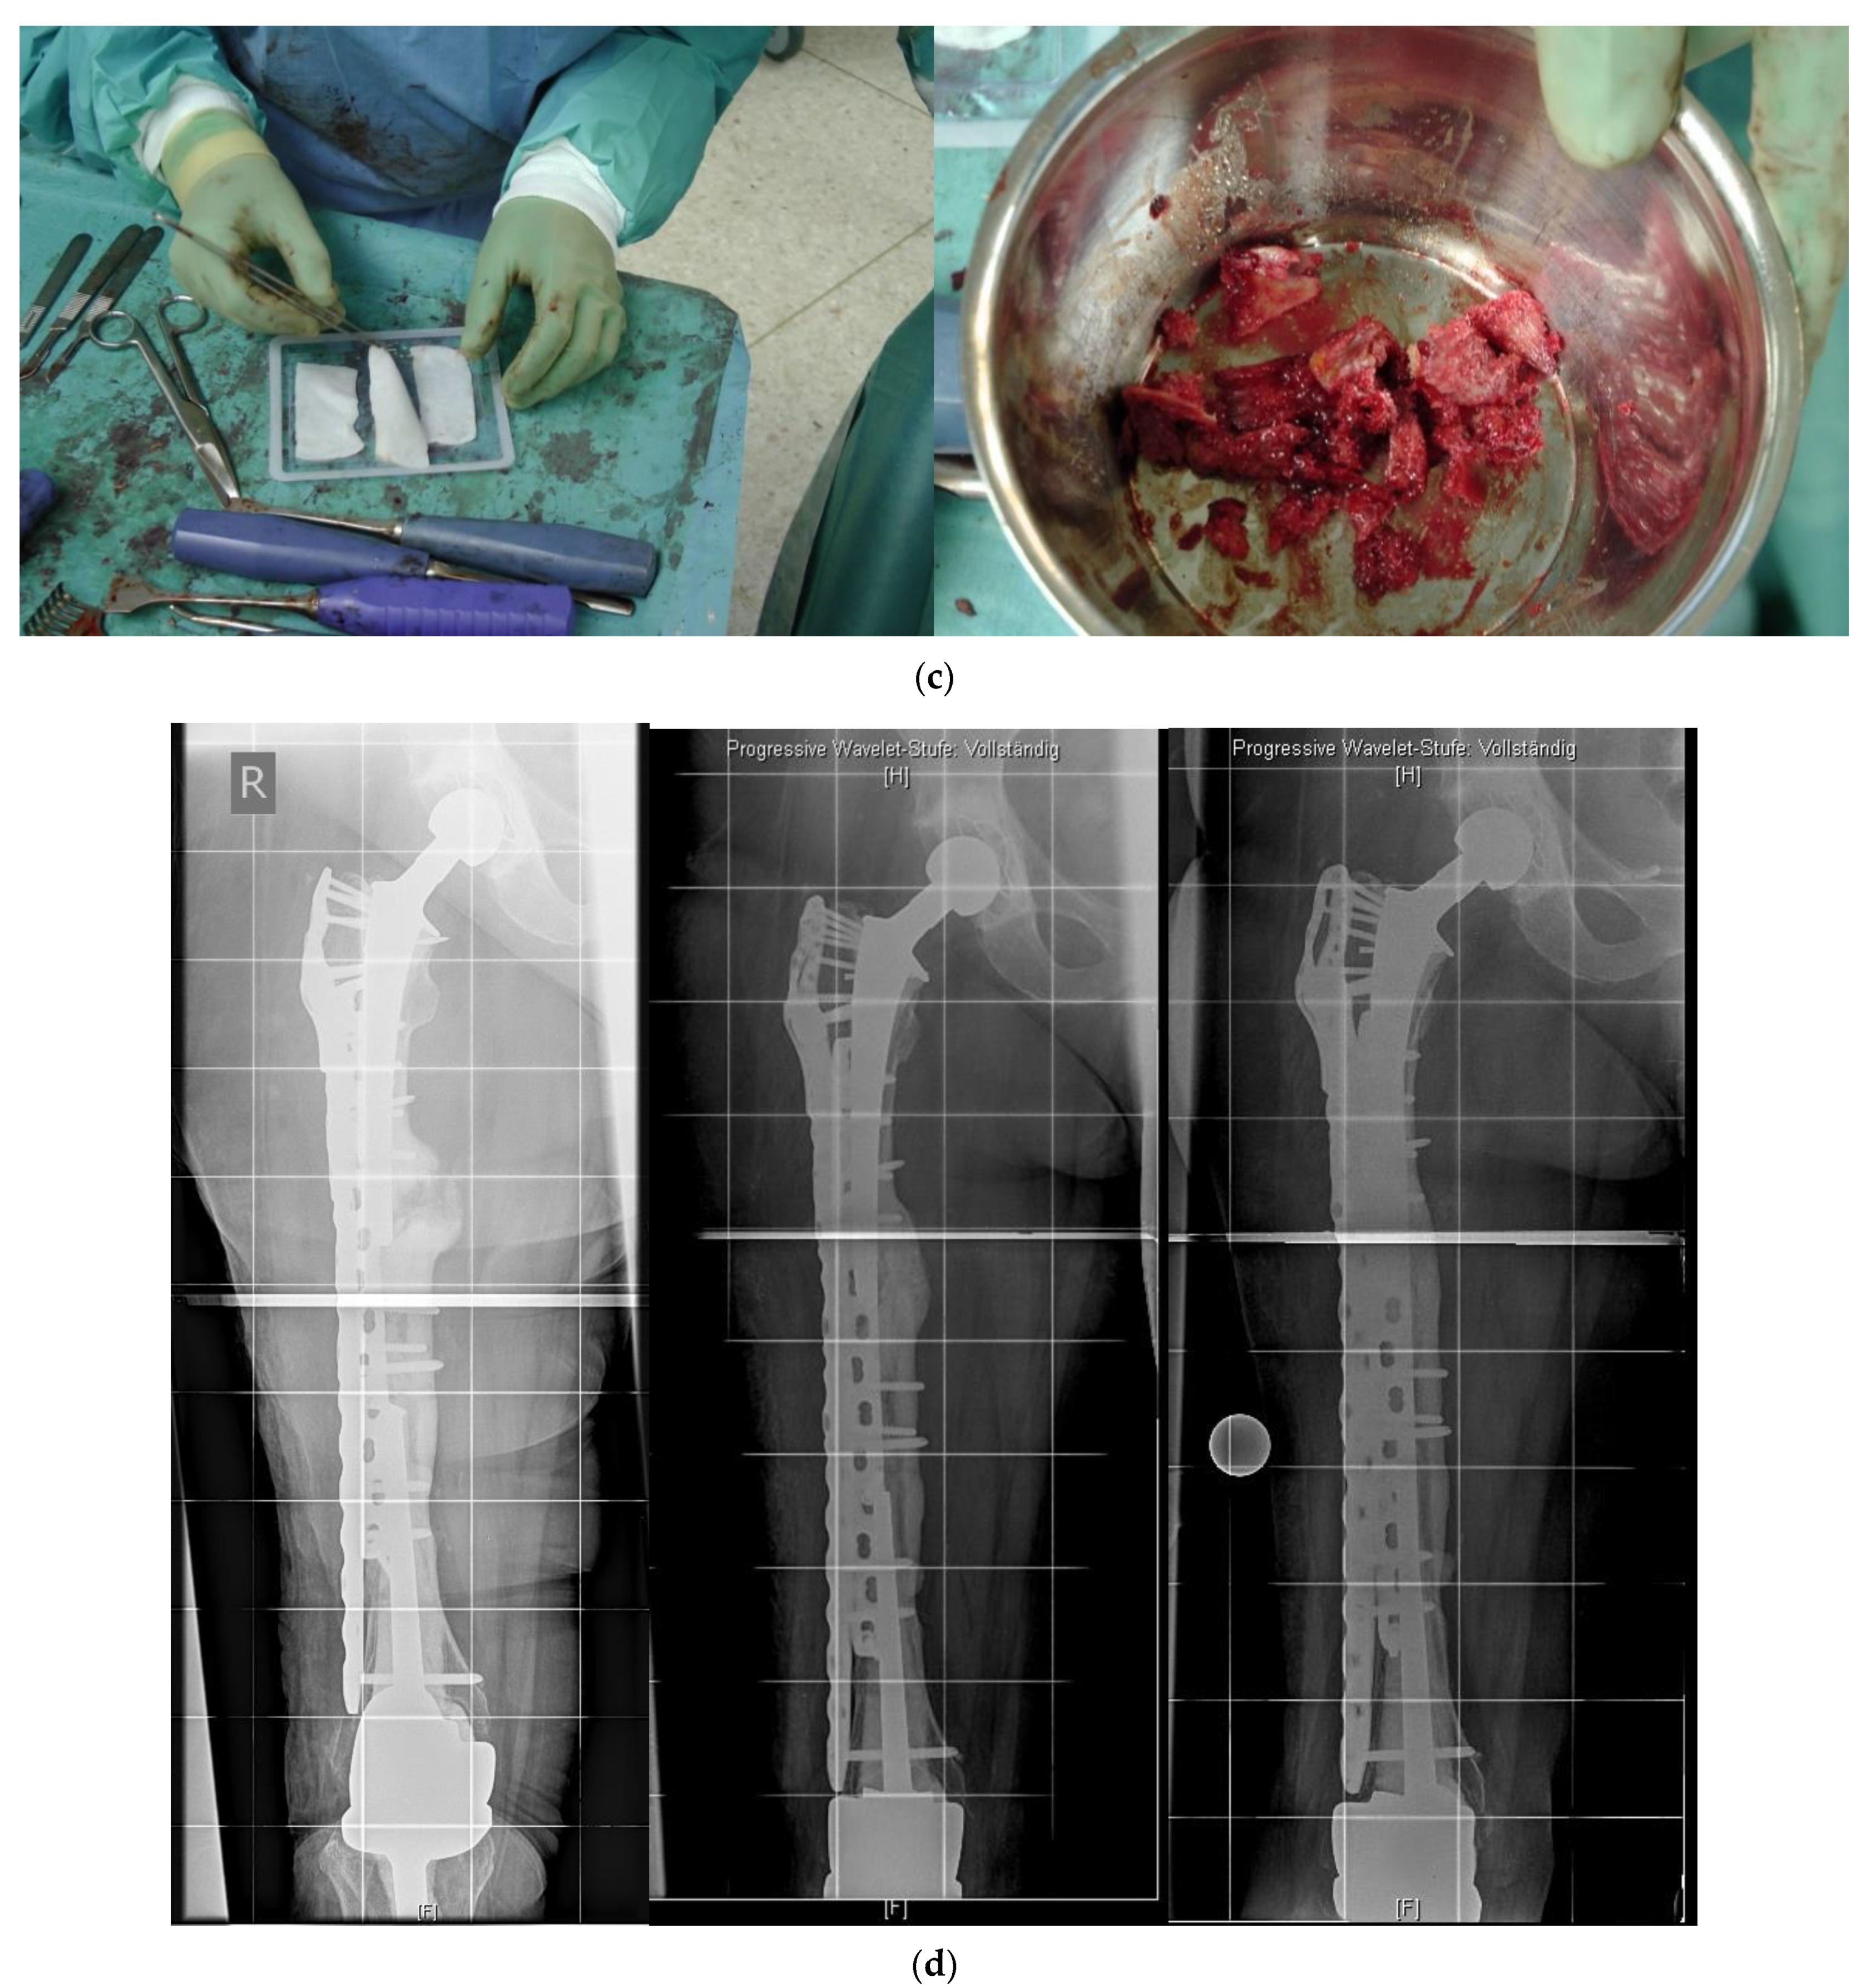

In revision cases and interprosthetic fractures, double plating is an alternative treatment option to avoid high-risk operations such as a total femur replacement. Figure 4 shows a successfully treated hypertrophic non-union after several interprosthetic re-fractures, using double plating in combination with autologous bone-grafting and growth factor application.

Figure 4.

(a) Interprosthetic hypertrophic non-union. Intraoperative situs showing the failed plate fixation and the non-union. (b) Intraoperative situs showing the double plating. (c) Double plating combined with bone-grafting and growth factor application. (d) Postoperative follow-up X-rays after 6 weeks, 12, and 24 months, demonstrating complete healing and remodeling of the fracture.